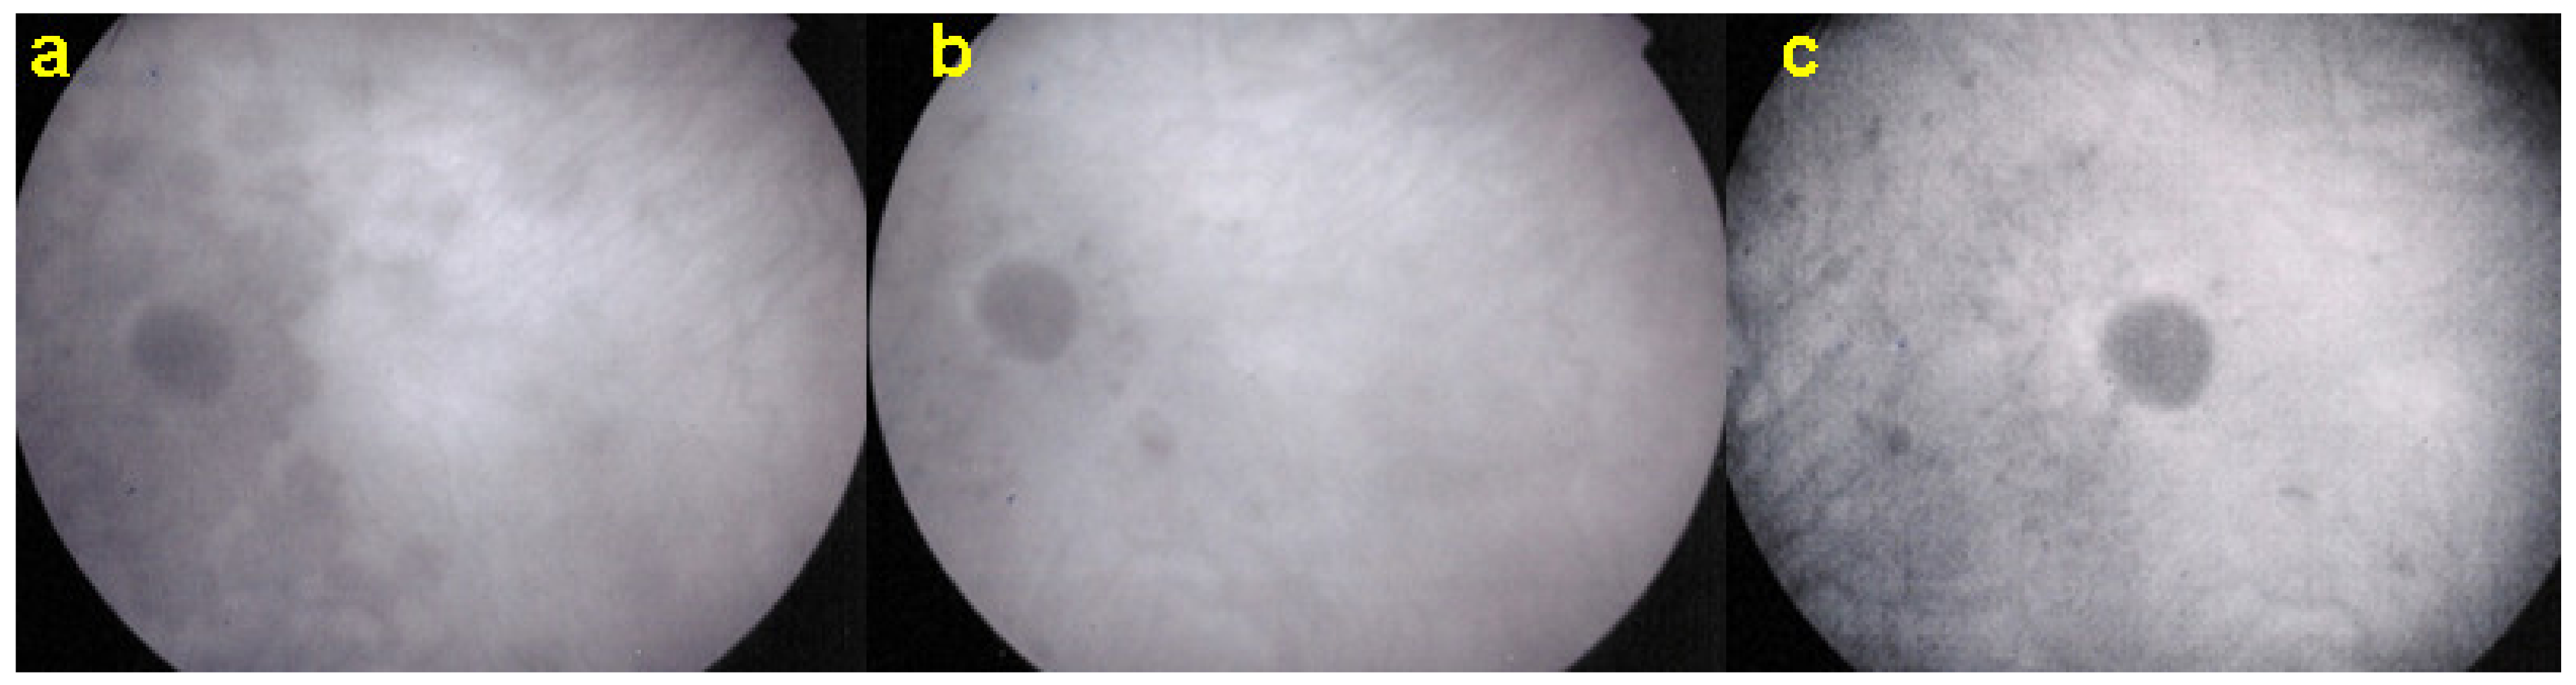

Acute macular neuroretinopathy (AMN) is a rare, outer retinal disease of unknown origin affecting typically young women who complain of paracentral scotomas mono or bilaterally and often occurring with oral contraceptive use. Visual loss is variable. As described by Bos and Deutman [77], the fundus examination reveals distinctive lesions characterized by macular reddish-brown, wedge-shaped lesions corresponding to scotomas referred by the patients (Figure 29).

However, these typical lesions are not always clearly visible on fundoscopy while they are seen more precisely when using the near infrared reflectance (NIR-R) imaging mode that demonstrates sharply demarcated, hyporeflective lesions more definite than those found on fundoscopy [78]. Blue-light fundus autofluorescence (488 nm, lipofuscin related) (BAF), fluorescein angiography (FA) and indocyanine green angiography (ICGA) are usually not significant, while near infrared autofluorescence (787 nm, melanin related) (NIR-FAF) can show abnormalities [78]. Together with the NIR-R, the spectral-domain optical coherence tomography (SD-OCT) represents a very useful new imaging technology to diagnose AMN demonstrating that the outer retina is primarily affected. In the early phase of the disease, OCT shows a transient, localized hyperreflectivity at the outer plexiform layer (OPL)/outer nuclear layer (ONL) [79] (Figure 30). In a short time, the hyperreflectivity is replaced by focal abnormalities of the ellipsoid zone (EZ) and interdigitation zone (IZ) that are often associated with thinning of the ONL (Figure 31 and Figure 32) In addition, electrophysiologic analysis also with multifocal electroretinography has clearly localized the lesion impact at the level of the outer retina [80]. AMN has good prognosis with a slow, progressive improvement of the symptomatology. Macular lesions can persist for a long time.

AMN is often put in the group of choriocapillaritis diseases, which is not the case. It is a rare macular disease of the outer retina. It can be unilateral or bilateral with an accompanying paracentral or central scotoma with or without visual loss. BAF, FA, and ICGA are mostly normal. Retinal capillary ischaemia has been proposed as a possible mechanism. SD-OCT findings suggest that the outer retina is the location of the pathology including hyper-reflectivity of the OPL and ONL, disruption of ellipsoid zone (EZ), and interdigitation zone (IZ) and subsequent thinning of the ONL. The introduction of OCTA has more clearly demonstrated retinal aetiology. As the patients are mostly young women, the main differential diagnosis for AMN is retrobulbar optic neuritis.